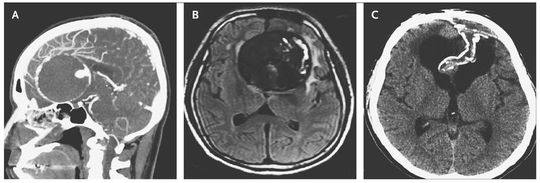

A 55-year-old man presented with a 3-year history of visual impairment associated with personality changes. His sister had died after an intracerebral aneurysmal rupture. An examination revealed poor visual acuity in the right eye with a field defect, as well as impaired neurocognition. Computed tomographic (CT) angiography (Panel A) and magnetic resonance imaging of the brain revealed a partially thrombosed, calcified, 7-cm aneurysm of the anterior communicating artery, with surrounding edema (Panel B). Thrombectomy and aneurysmal repair were performed to reduce the risk of aneurysmal rupture and to alleviate the mass effect. The patient recovered from surgery and had improvement in his neurocognitive deficits and vision, and he was able to return to work. His condition remained stable 2 years later, and delayed CT showed collapse of the aneurysmal sac (Panel C). Giant aneurysms (>2.5 cm) represent a small proportion of brain aneurysms but are associated with a high rupture rate when left untreated. Approximately 20% of patients with a brain aneurysm have a first-degree relative with a brain aneurysm.